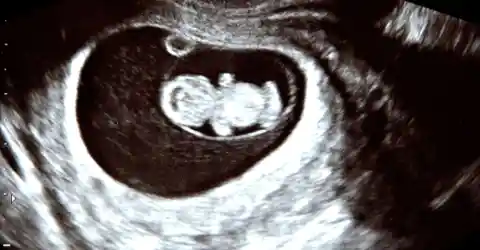

The pathologist sat across from Sarah and Mark, eyes steady. “Your tissue contains fetal DNA,” she said softly. “We identified genetic markers that don’t match your own. In other words, you have retained fetal tissue.”

The doctor explained a rare medical phenomenon—when a pregnancy implants outside the uterus (an abdominal or ectopic pregnancy), the fetus can die and be too large to be reabsorbed. The body sometimes calcifies the remnant to isolate it—a lithopedion, or ‘stone fetus’—allowing it to remain for years. Recent medical literature documents retained calcified fetal remnants lasting decades, with retention times reported from a few years to many decades.

How It Happens

The doctor continued gently: an abdominal ectopic pregnancy can progress undetected if it doesn’t cause immediate catastrophic bleeding. When the fetus dies and cannot be expelled or reabsorbed, the immune system may deposit calcium around it, essentially “walling it off.”

This calcification prevents infection and inflammation, and a remnant can remain asymptomatic for years. Though extremely rare, fewer than a few hundred cases have been reported worldwide; clinicians rely on imaging and pathology, including DNA testing, for diagnosis.